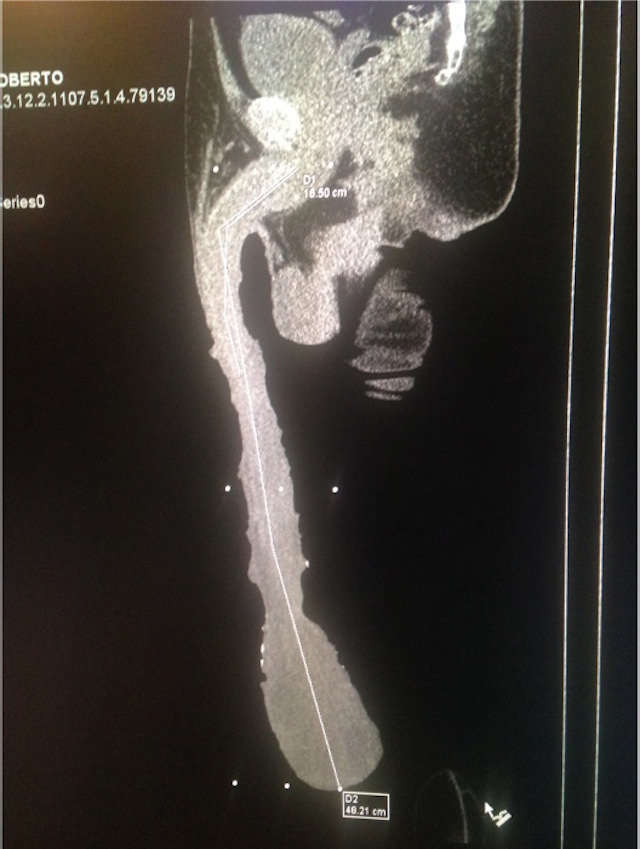

En febrero de este año Roberto se presenta en la redacción de un diario mexicano donde se le practican mediciones y se le acompaña a realizarse tomografías y radiografías. 48,2 centímetros es la medida oficial, 14 más que la polla de Jonah Falcon, considerada hasta hace poco la más larga del mundo.